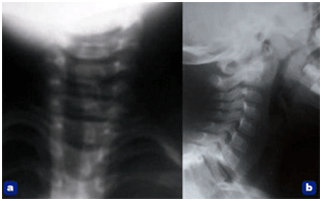

Figure 1. – Clichés cervicaux de face (a) et de profil (b).

On ne note pas de ruptures de courbure du rachis cervical ni d’épaississement des parties molles.

Les clichés cervicaux (figure 1), réalisés devant la notion initiale de traumatisme, sont normaux. Le bilan biologique montre un syndrome inflammatoire (encadré).